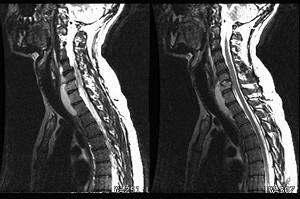

问题 男,38岁,颈部疼痛伴低热1月余,曾有结核病史,结合MRI图像,最可能的诊断是 ( )

选项 A、颈椎骨转移瘤 B、食管异物并感染 C、颈椎体结核 D、咽后脓肿 E、颈椎体结核及咽后脓肿

答案 E